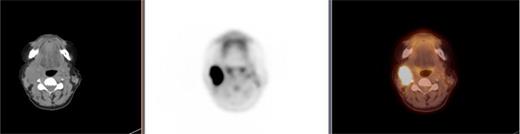

On imaging with computed tomography (CT) of the neck and chest, an asymmetrically enhancing soft tissue mass was seen in the right glossotonsillar sulcus, with associated ipsilateral right-sided level 2A lymphadenopathy (Fig. 1). Positron emission tomography (PET) demonstrated hypermetabolism in the right glossotonsillar sulcus, which was consistent with the primary site and evidence of distant metastases (Fig. 2). The patient was reviewed in the Head and Neck clinic and was staged on imaging as T1 N2b M0.

PET scan showing metastatic disease in the right level 2A lymph nodes.